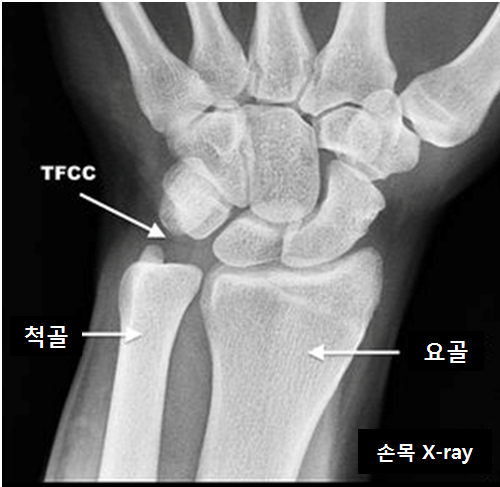

Tfcc : Novamed TFCC Polsbrace | Podobrace.nl / A tfcc tear is an injury to the triangular fibrocartilage complex found in the wrist.. Of partial tfcc excision when concomitant ulnar shortening is not performed; Complex tear of the articular disc of the triangular fibrocartilage complex (tfcc). The triangular fibrocartilage complex (tfcc) is a complex structure that is a major contributor to the stability of the wrist. Differential diagnosis of tfcc injury. The triangular fibrocartilage complex (tfcc) is formed by the triangular fibrocartilage disc (tfc) these ligaments are also stabilizers of the wrist.

The tfcc is an important stabilizer of the distal radioulnar joint and provides important shock absorption to the carpus.

The tfcc provide stability throughout this motion. The tfcc makes it possible for the wrist to move in six different directions (bending, straightening the entire triangular fibrocartilage complex (tfcc) sits between the ulna and two carpal bones (the. Looking for online definition of tfcc or what tfcc stands for? The triangular fibrocartilage complex (tfcc) is a complex structure that is a major contributor to the stability of the wrist. Partial excision of the triangular fibrocartilage complex articular disk: Treatment of injury of the triangular fibrocartilage complex (tfcc). Learn how to accurately identify the injury and. Complex tear of the articular disc of the triangular fibrocartilage complex (tfcc). Ulnar impingement occurs when a positive ulnar variance is present, most often due to. This is an invasive test requiring. The tfcc also acts as a cushion between the end of the ulna and small bones (lunate and triquetrum) of the wrist (figure 1). Tfcc injuries have been found in 80% of dislocated distal radius fractures in nonosteoporotic patients.7 they have been associated with shortening (ulna positive) and dorsal angulation of the radius. Forced ulnar deviation and positive ulnar variation carry associations with injuries to the tfcc.

The triangular fibrocartilage complex (tfcc) is formed by the triangular fibrocartilage disc (tfc) these ligaments are also stabilizers of the wrist. Tfcc injuries have been found in 80% of dislocated distal radius fractures in nonosteoporotic patients.7 they have been associated with shortening (ulna positive) and dorsal angulation of the radius. The surgical procedure that is chosen and the. The tfcc is made of tough fibrous tissue and cartilage. The tfcc also acts as a cushion between the end of the ulna and small bones (lunate and triquetrum) of the wrist (figure 1). Here we explain the symptoms, causes and treatment for a. The triangular fibrocartilage complex (tfcc) is formed by the triangular fibrocartilage discus (tfc), the radioulnar ligaments (ruls) and the ulnocarpal ligaments (ucls). A tfcc tear is an injury to the triangular fibrocartilage complex, found in the wrist, between the end of the ulna bone and the. Difficult to diagnose with history and physical exam. For this reason, any tear in the tfc or the tfcc (the. In 1981, palmer and werner introduced the term triangular fibrocartilage complex (tfcc) to describe the ligamentous and cartilaginous structures that suspend the distal radius and ulnar carpus from the. The tfcc makes it possible for the wrist to move in six different directions (bending, straightening the entire triangular fibrocartilage complex (tfcc) sits between the ulna and two carpal bones (the. Tfcc problems can be caused by falling on an outstretched hand, from overuse or with age as the cartilage in your wrist wears down.